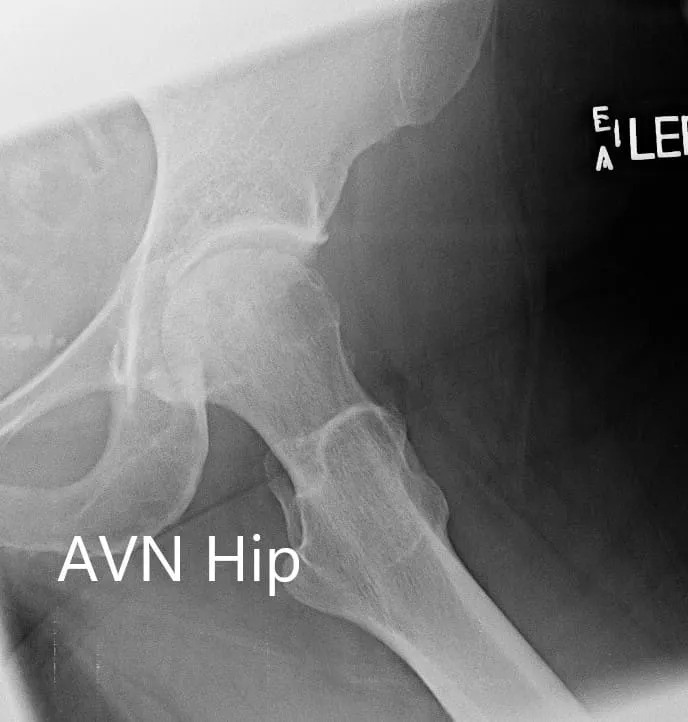

Las imágenes revelaron cambios osteoartríticos en la cadera izquierda con una lesión de la RNV que afecta al 60% de la cabeza femoral. Se realizó una resonancia magnética que reveló necrosis avascular femoral izquierda sin colapso subcondral evidente.

Radiografía que muestra la vista AP de la pelvis con ambas articulaciones de la cadera

Radiografía que muestra las vistas AP y laterales de pata rana de la articulación de la cadera izquierda